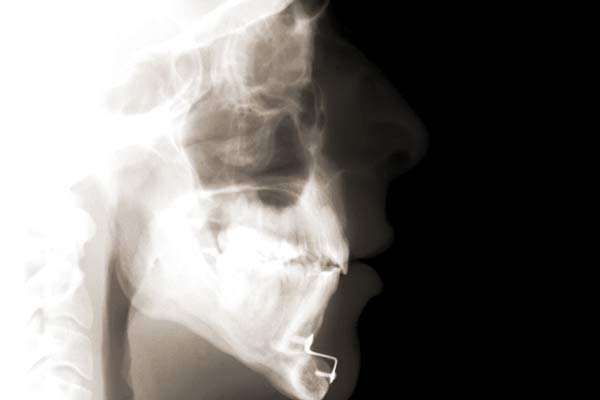

Digitales Röntgen - Fernröntgenseitenbild (FRS)

Das Fernröntgenseitenbild gibt dem Kieferorthopäden Aufschluss über die Art der Kiefereinlagerung im Gesichtsschädel des Patienten, zeigt die Achsenneigung der Frontzahnwurzeln und gibt zudem Hinweise über die Wachstumsrichtung des Ober- bzw. Unterkiefers. Durch eine Darstellung der anatomischen Gegebenheiten, die durch Winkel und Strecken computerunterstützt ergänzt werden, wird es dadurch möglich wichtige Rückschlüsse für die Behandlungsplanung zu erhalten.